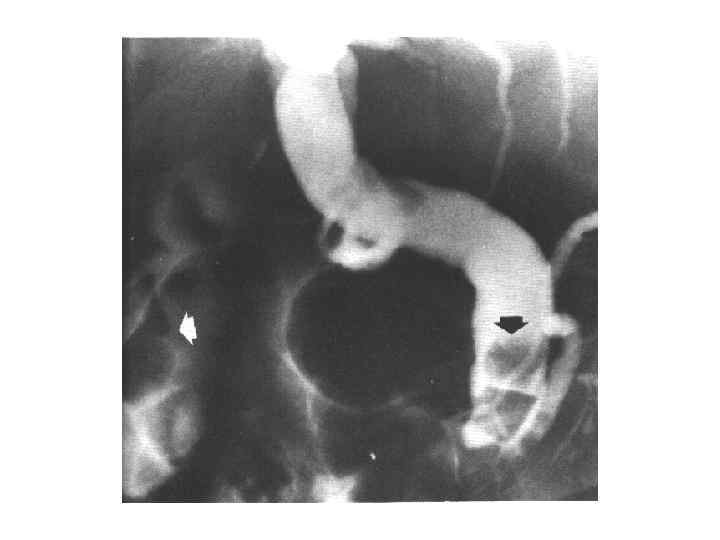

Диагностика • • • Сбор анамнеза Осмотр Обследование передней брюшной стенки Люборатоные данные: общий анализ крови; биохимическое исследование крови, Дуоденальное зоондирование с бактериологическим исследованием всех порций желчи Рентгенологическое исследование УЗИ КТ РХПГ ФЭГДС Лапароскопия радиоизотопное исследование

Диагностика • • • Сбор анамнеза Осмотр Обследование передней брюшной стенки Люборатоные данные: общий анализ крови; биохимическое исследование крови, Дуоденальное зоондирование с бактериологическим исследованием всех порций желчи Рентгенологическое исследование УЗИ КТ РХПГ ФЭГДС Лапароскопия радиоизотопное исследование